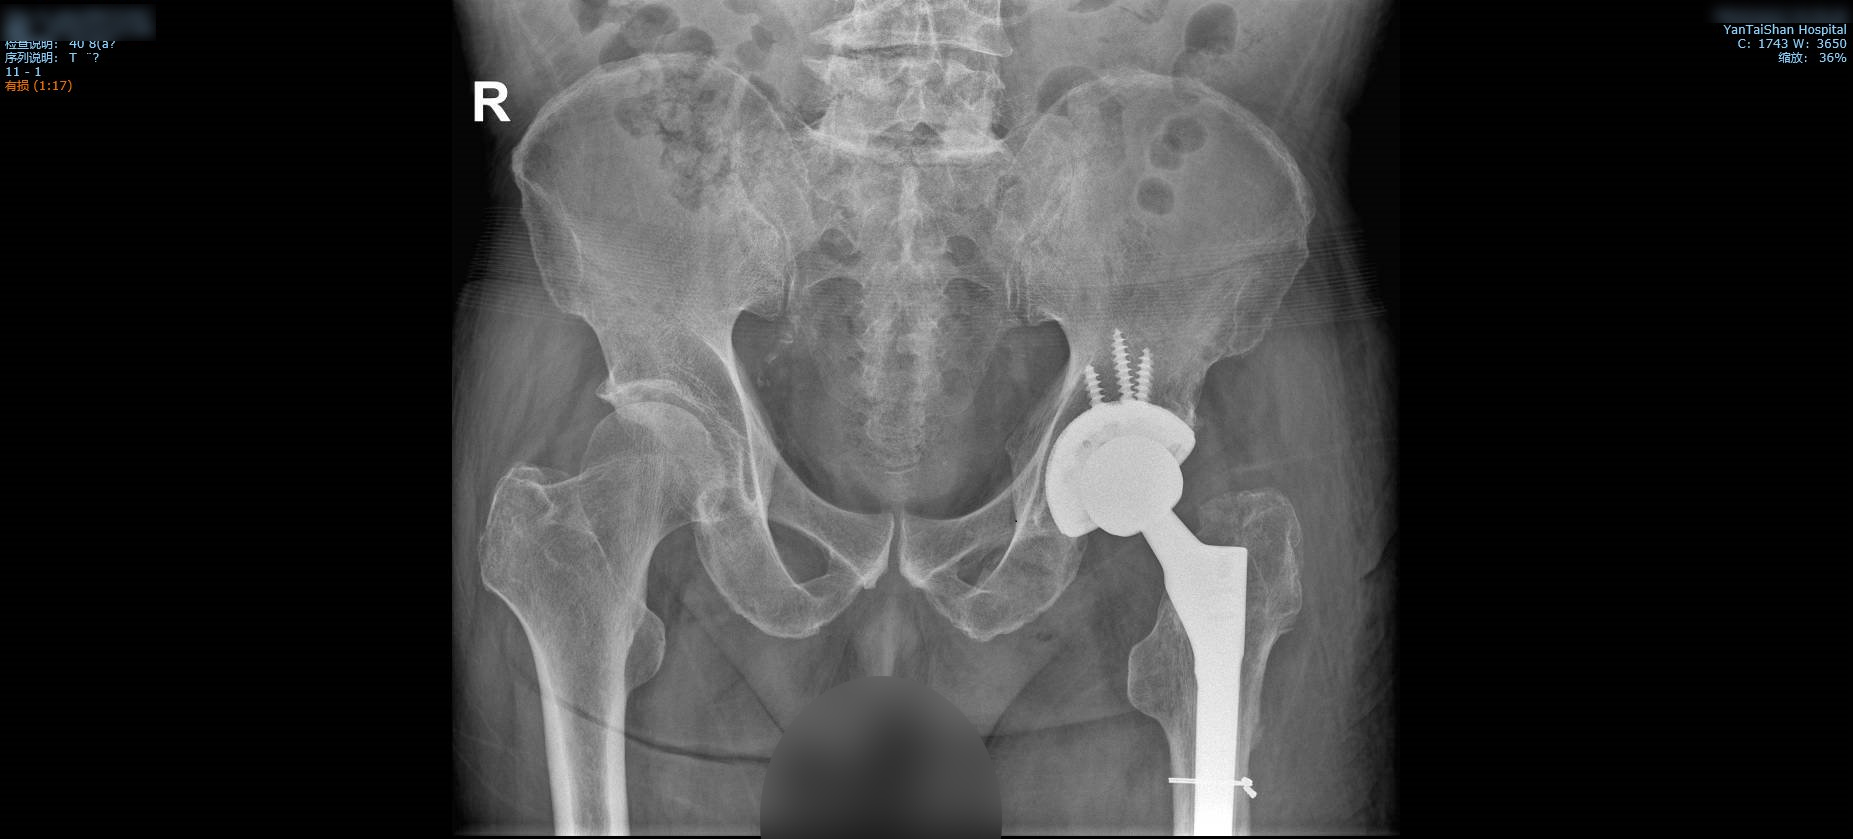

术后正、侧位影像。

术后全髋影像。